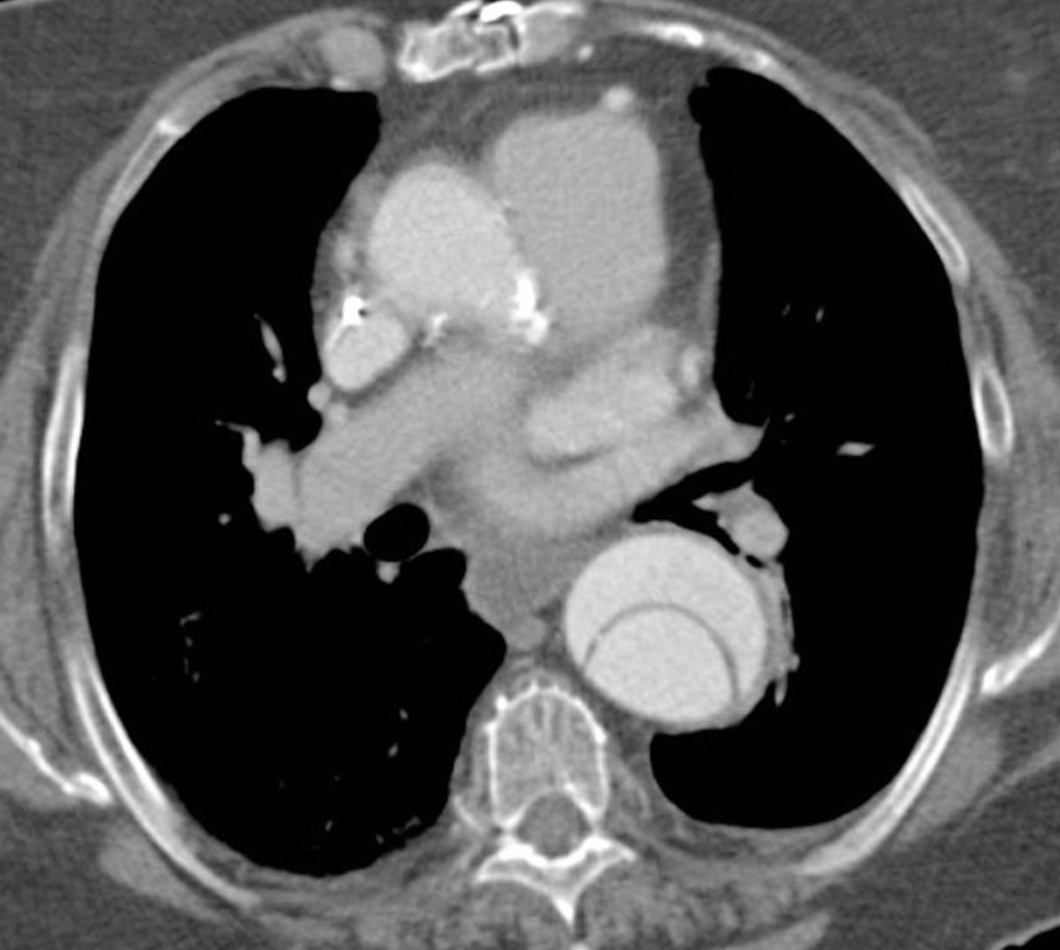

What type of aortic dissection can be seen on this image?

A

Type B

Can see flap in desecending aorta